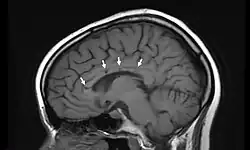

Sagittal T1 image in a 19-year-old woman with Susac's syndrome showing the pathognomonic central callosal "holes" (microinfarcts) of SS. These residual "holes" (and sometimes, "spokes") develop as the acute callosal changes resolve. | |

In a recent analysis (Susac et al., 2003), MRI images from 27 patients fulfilling the diagnostic criteria of Susac's syndrome were reviewed. Multifocal supratentorial lesions were present in all patients. Most lesions were small (3 to 7 mm), though some were larger than 7 mm. All 27 patients had corpus callosum lesions. These all had a punched-out appearance on follow-up MRI. Though most commonly involving white matter, many patients also had lesions in deep grey matter structures, as well as leptomeningeal enhancement. Multiple sclerosis (MS) and acute disseminated encephalomyelitis (ADEM) can mimic the MRI changes seen in patients with Susac's syndrome. However, the callosal lesions in Susac's syndrome are centrally located. In comparison, patients with MS and ADEM typically have lesions involving the undersurface of the corpus callosum. Deep gray matter involvement commonly occurs in ADEM but is very rare in MS. Leptomeningeal involvement is not typical of either MS or ADEM: if 10 lesions are found in the brain of an MS patient, a lesion may be found in the corpus callosum. If a Susac patient has 10 lesions, more than half will be in the corpus callosum.